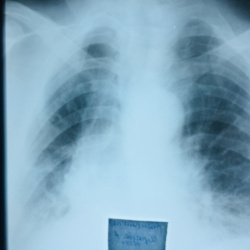

Добрый день. Пациент температурит пятый день, до 39. Терапевт аускультативно слышит и ослабление, и жёсткое дыхание, причём с 2-х сторон, ожидали пневмонию на снимке, но я не вижу. Хотела придраться...